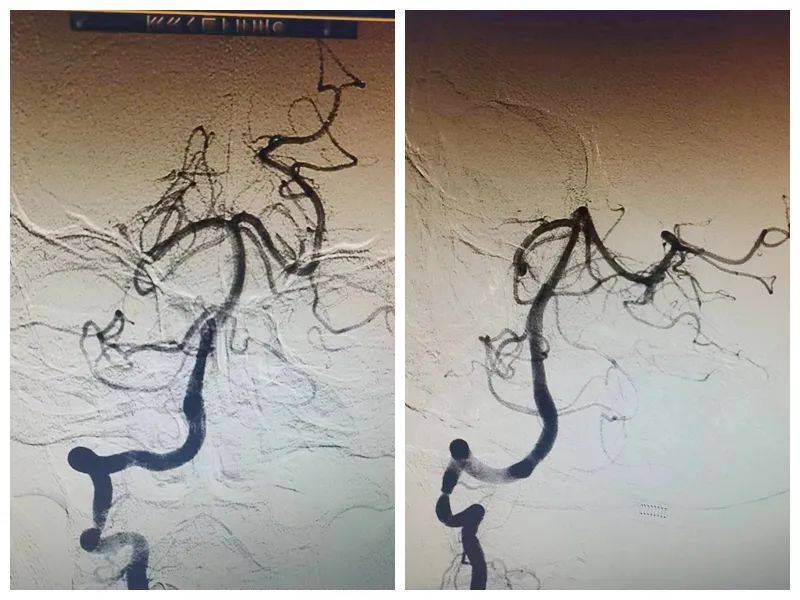

术后第二天复查颅脑CTA

虽然手术顺利完成了,但患者仍未完全脱离危险,再灌注损伤和脑水肿将是卒中的下一个困难关卡,这是一场生命与死神的博弈。神经内科卒中团队立即制定了详细的治疗方案,尽最大能力降低患者致死、致残率,帮助患者早日回归家庭,回归社会。经过3天的治疗与照护,张先生终于逐渐从昏睡中苏醒过来,偏瘫的肢体也恢复了运动能力,一周后患者已经可以通过搀扶下床活动。